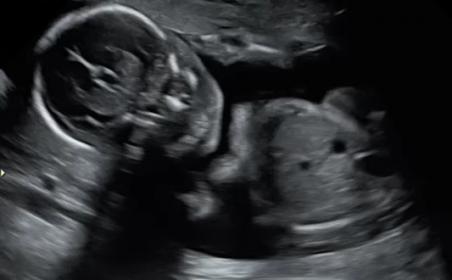

Team Green No Longer ??? 20 week scan

Hi! I recently went to my 20 week scan with the intention of being team green! All went well during the scan and I didn't see any definitive "bits". The pictures the tech sent me didn't seem to give any clues....but then I make the mistake of watching the DVD with live shots. I seems like there is a brief glimpse of boy parts in the shot where the baby is facing forward. It looks like a potty shot, but I haven't seen any with the skull visible, so I am not sure what to think. I'm hoping that I am still team green, but these shots make me think otherwise. Any insight would be greatly appreciated!! I am going crazy trying to figure it out. :shrug:

Attachment 42608Attachment 42609Attachment 42610